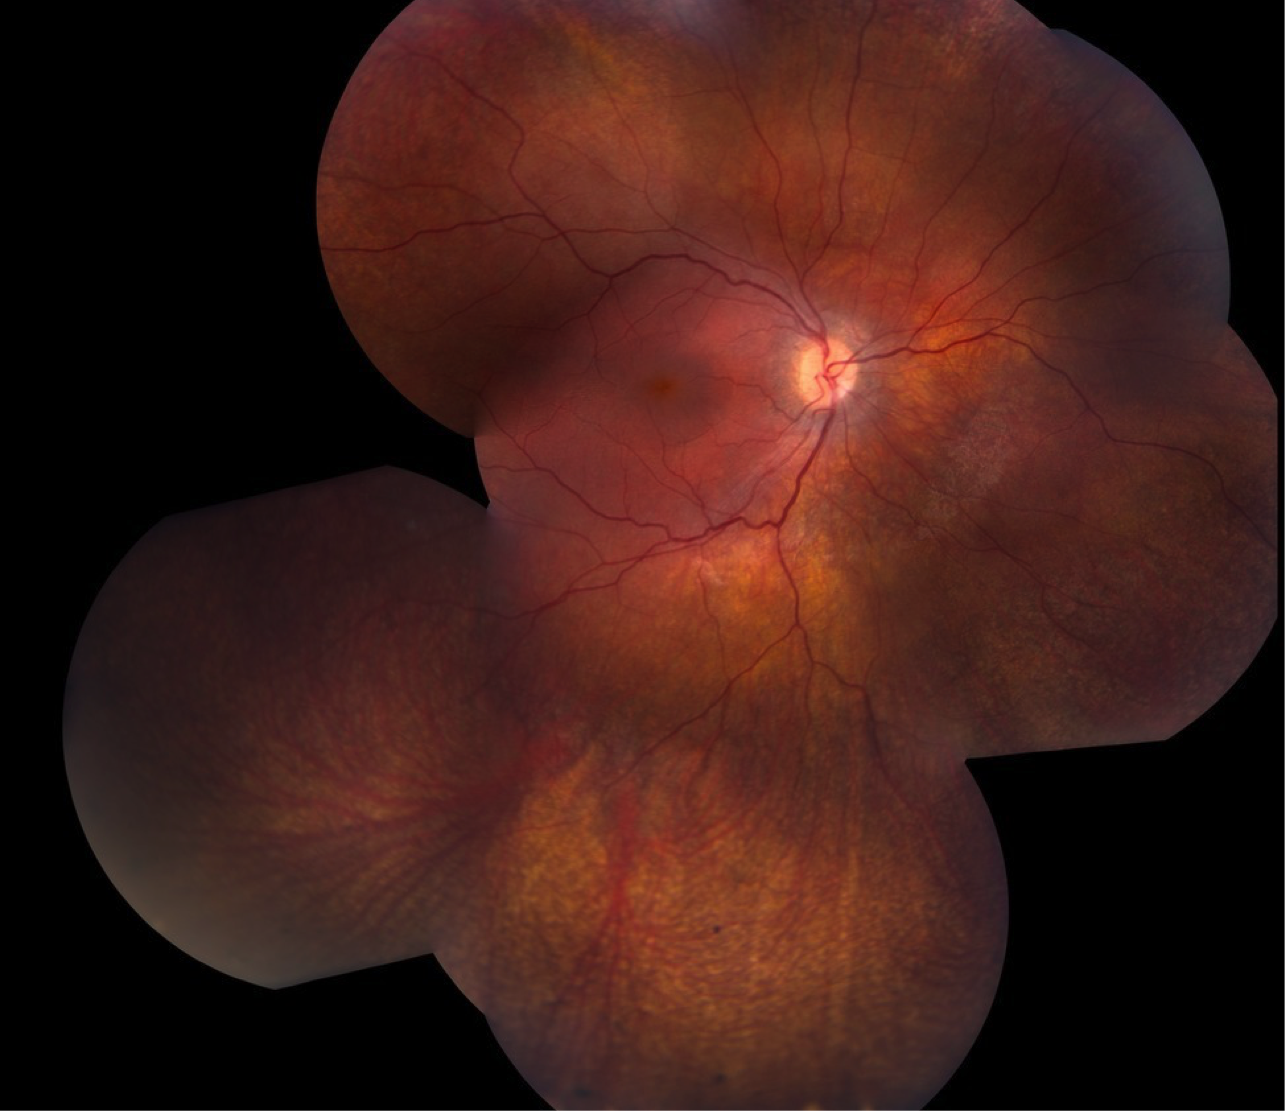

Case 9 is a six year old girl who was visually inattentive and had pronounced nystagmus at 4 months of age. An electroretinogram was performed at that time and no responses could be detected under any stimulus conditions. Her parents have normal vision. On our examination, her visual acuity was 20/80. Streak retinoscopy revealed about 5 diopters of hyperopia.

Color fundus photograph of the right eye.